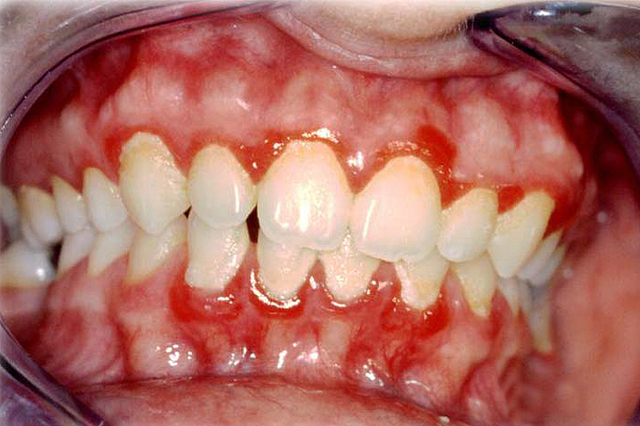

• Pierre Charles Alexander Louis, condujo gran cantidad de estudios demostrando tuberculosis no se transmitía hereditariamente y que la sangría era inútil.

Pierre Charles Alexander Louis, condujo gran cantidad de estudios demostrando tuberculosis no se transmitía hereditariamente y que la sangría era inútil.